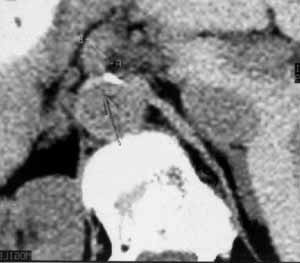

Рис. 7. КТ-томограмма. Кальцинированная бляшка в устье чревного ствола. Атеросклероз брюшной аорты.